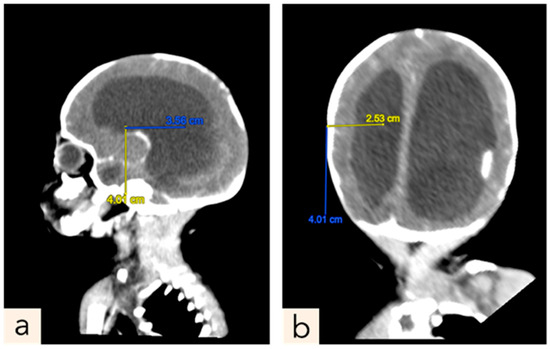

2.1. Patient 1

2.2. Patient 2

2.3. Patient 3

2.4. Patient 4